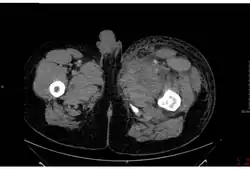

Despite signing the 1972 agreement to end bioweapon production, the government of the Soviet Union had an active bioweapons program that included the production of hundreds of tons of anthrax after this period. On 2 April 1979, some of the over one million people living in Sverdlovsk (now called Ekaterinburg, Russia), about 1,370 kilometres (850 mi) east of Moscow, were exposed to an accidental release of anthrax from a biological weapons complex located near there. At least 94 people were infected, of whom at least 68 died. One victim died four days after the release, 10 over an eight-day period at the peak of the deaths, and the last six weeks later. Extensive cleanup, vaccinations, and medical interventions managed to save about 30 of the victims.[113] Extensive cover-ups and destruction of records by the KGB continued from 1979 until Russian President Boris Yeltsin admitted this anthrax accident in 1992. Jeanne Guillemin reported in 1999 that a combined Russian and United States team investigated the accident in 1992.[113][114][115]

Nearly all of the night-shift workers of a ceramics plant directly across the street from the biological facility (compound 19) became infected, and most died. Since most were men, some NATO governments suspected the Soviet Union had developed a sex-specific weapon.[116] The government blamed the outbreak on the consumption of anthrax-tainted meat, and ordered the confiscation of all uninspected meat that entered the city. They also ordered all stray dogs to be shot and people not have contact with sick animals. Also, a voluntary evacuation and anthrax vaccination program was established for people from 18 to 55.[117]